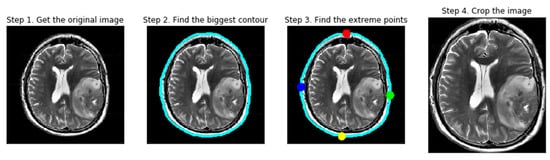

Data preparation is a critical component of medical image analysis, as it directly influences model accuracy and robustness. In this study, MRI images underwent a series of preprocessing steps—including contour-based cropping, dilation, and erosion—to reduce noise and artifacts and to enhance classifier performance. Cropping was conducted using a contour detection system that identifies extreme points and curves to isolate the region of interest. Figure 2 presents representative examples of cropped brain tumor images obtained using parameter-based calculations.

Although the present framework is limited to MRI-based analysis, it has the potential to incorporate additional biomechanical features and multimodal data in future research, such as integrating ultrasound imaging to improve diagnostic precision. As illustrated in Figure 3, raw MRI images from the BR35H dataset were imported and subjected to preprocessing. Initially, all RGB images were converted to grayscale, followed by binary conversion through thresholding. Subsequently, dilation and erosion operations were applied to minimize minor interferences and enhance structural boundaries. Contours were then detected on the thresholded images, and the largest contour was selected to determine the extrema points, which were used to crop the final region of interest.